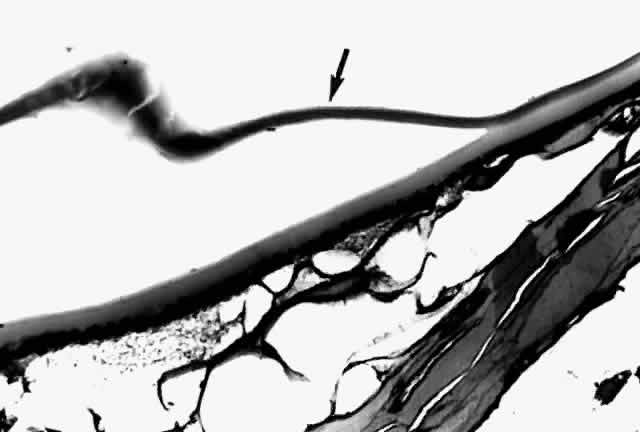

Histologic examination shows an unequal splitting of the anterior capsule (Fig. 1). Electron microscopic examination shows that the lens capsule is laminated and the anterior layer or layers are split free.29 The free portion is quite thin, and it can be rolled or folded over.27

Fig. 1. True exfoliation of the lens capsule. The anterior lens capsule is split and floats away from the rest of the lens (arrow). The subepithelial disruption is artifact. (H & E, magnification × 234; Courtesy of Dr. W.R. Green, Baltimore, MD)